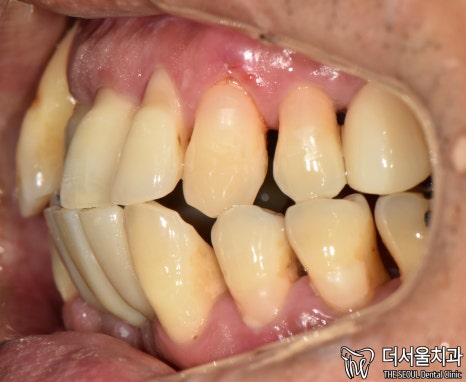

먼저 사진을 보겠습니다.

여러분이 보더라도

구강 상태가 심각하다는 걸 알 수 있습니다.

올바른 교합이 이뤄질 수 없을 뿐더러

치경부 마모증에 쌓여있는 치석에 충치까지

손댈 부분이 너무 많네요.

게다가 구취까지 나고 있었기에

걱정되는 상황이었습니다.